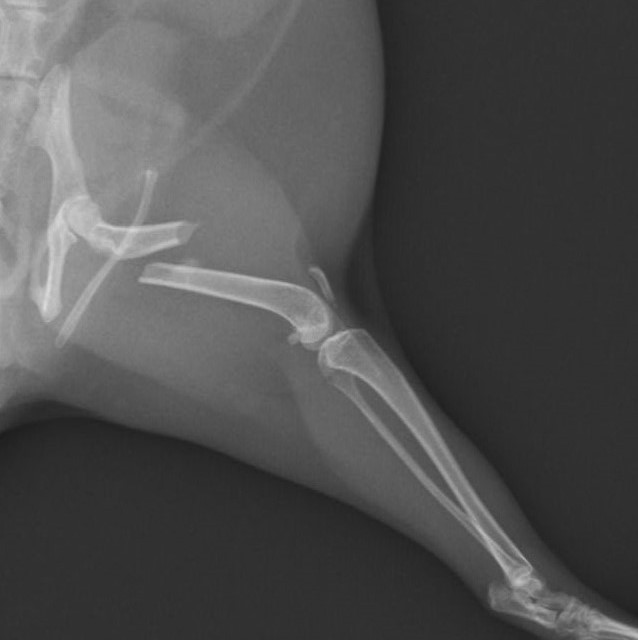

大腿骨骨折のフェレットちゃんの手術依頼でご紹介がありました。TAITAN1.2プレートを使用し無事歩けるようになりました。よかったね。